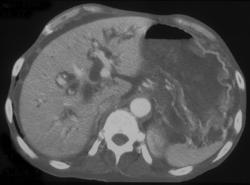

Ulcerating Adenocarcinoma of the Stomach With Liver Matastases